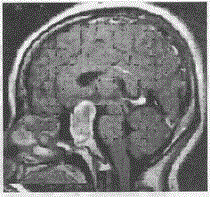

问题 女,36,闭经半年,核磁强化如图,最可能的诊断是

选项 A.颅咽管瘤 B.脊索瘤 C.神经鞘瘤 D.垂体瘤 E.蝶窦黏液囊肿

答案 D